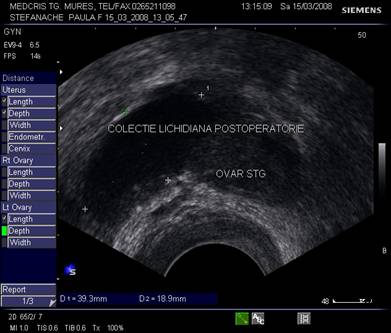

Fig. nr.403. Uter cu sac gestational, anterior vezica urinara in pozitia conventionala. Se remarca o zona anecogena in regiunea intervezicouterina ( colectie lichidiana postoperatie cezariana)